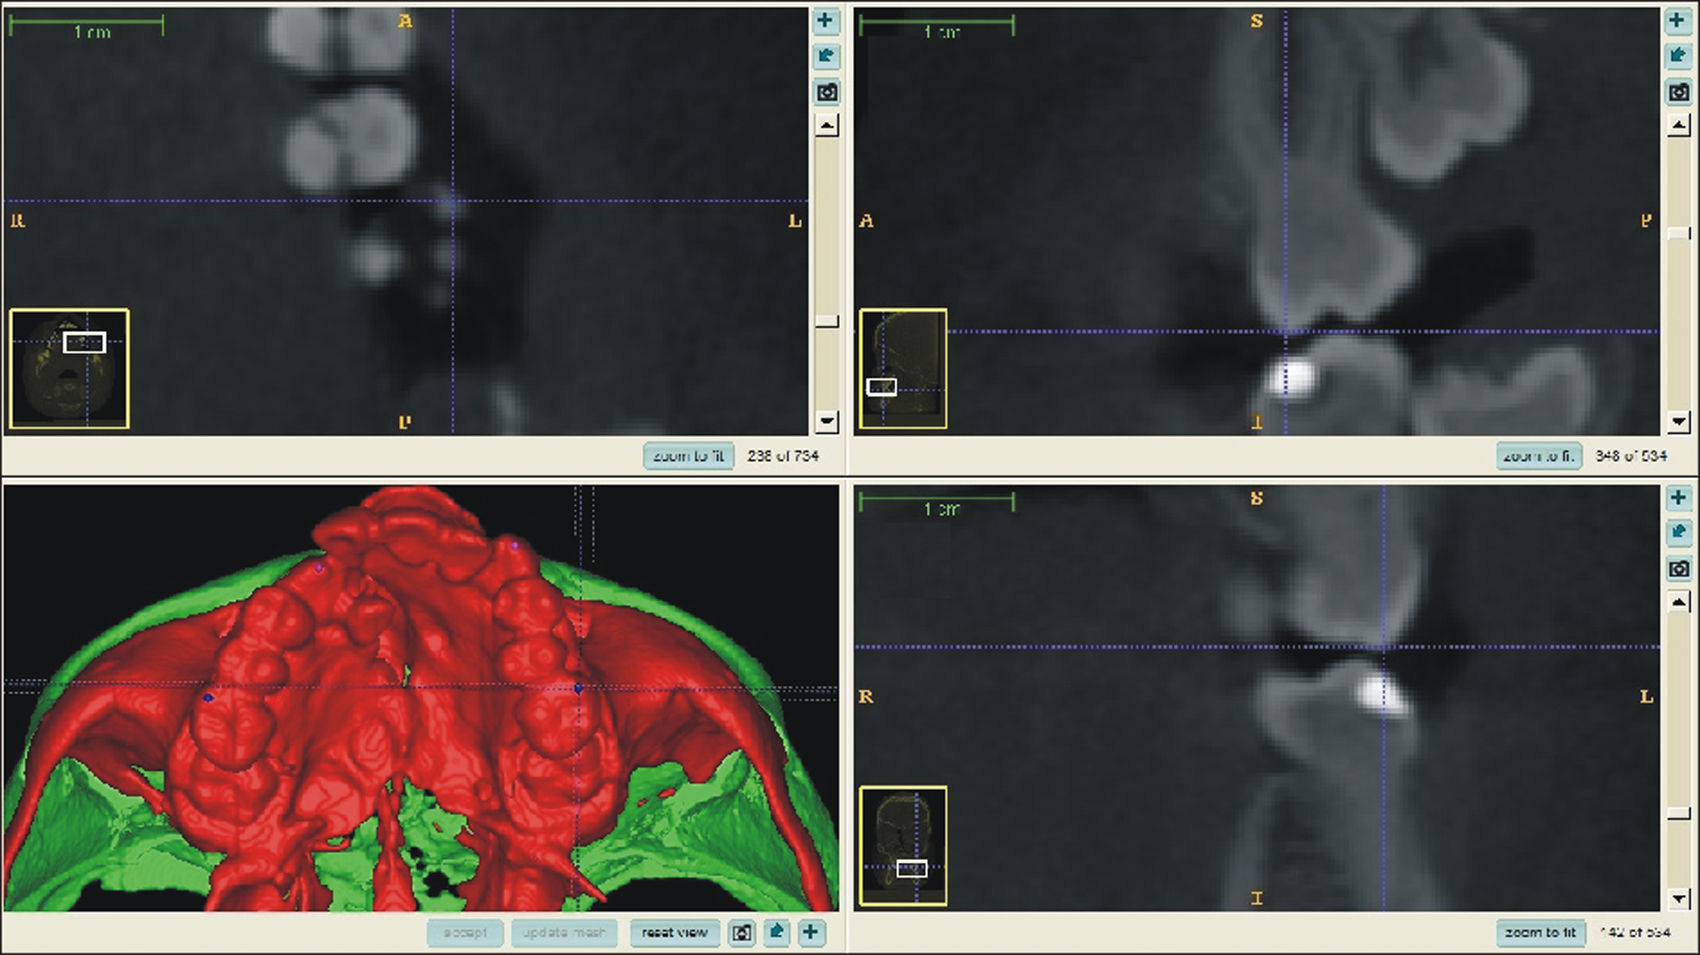

O surgimento e o aumento da acessibilidade da TCFC agregaram uma maior credibilidade ao diagnóstico clínico e às investigações científicas no estudo das deformidades craniofaciais19. Todavia, as informações 3D fornecidas pelas TCFC ainda vêm sendo rotineiramente analisadas de forma 2D, por medidas lineares em cortes ortogonais5,20. A construção e sobreposição de modelos virtuais 3D ainda é uma metodologia pouco difundida. Este estudo é um dos pioneiros que utiliza este método para avaliação de ERM em pacientes com fenda. A sobreposição baseia‐se na construção dos modelos virtuais 3D, utilizando o software SLICER21, pelos arquivos obtidos na TCFC, seguida pela sua justaposição, que utiliza a base do crânio como referência e a final obtenção dos métodos de medidas intitulados: sobreposição por semitransparência e mapa por códigos de cores22. A sobreposição por semitransparência revela uma análise qualitativa, em que o momento pós‐tratamento é retratado por uma malha preta translúcida, sobre o modelo inicial em vermelho (figs. 9 e 10). O aparelho em leque demonstrou um deslocamento de quase todos os dentes para vestibular e uma movimentação vestíbulo‐posterior do segmento menor (lado esquerdo [fig. 9]). O mapa por códigos de cores permite um complemento da análise visual, sendo que cada cor reflete uma alteração na posição das estruturas: azul – recuo; verde – estabilidade e vermelho – expansão. A intensidade da cor está diretamente relacionada à quantidade de movimentação. Todo o mapa é seguido por uma escala, com os valores em milímetros para cada cor (figs. 11 e 12). A observação feita na sobreposição por semitransparência do expansor em leque é confirmada no mapa por código de cores e nas medidas lineares. Uma menor porção de vermelho é visualizada em molares, quando comparada aos pré‐molares. O deslocamento para posterior e vestibular do menor segmento é constatado pela presença de azul na mesial dos dentes e vermelho nas eminências alveolares do lado em questão. Diferentes tonalidades de azul são vistas na cervical dos incisivos, possivelmente uma retroinclinação em decorrência da ausência de apoio mecânico no local. Para a quantificação das mudanças no posicionamento dentário, primeiramente identificou‐se, nos 3 cortes ortogonais, os pontos de referência para a medida (ponta da cúspide mésio vestibular dos primeiros molares superiores e ponta da cúspide dos caninos), tanto do lado direito como do lado esquerdo, utilizando o software ITK Snap23. Os pontos foram marcados com uma esfera de 0,5mm de diâmetro, identificando a posição 3D destas referências no espaço (fig. 13). A aferição das distâncias Euclidianas entre as esferas foi realizada com o auxílio da ferramenta Q3DC no programa SLICER23. O paciente A obteve um aumento de 3mm na distância intercanina e de 6mm na distância intermolar. Na elucidação do paciente que utilizou o disjuntor mini‐Hyrax invertido com BTP (B), observa‐se na sobreposição por semitransparência um deslocamento vestibular, principalmente dos pré‐molares e uma constância das demais áreas, achados corroborados no mapa por código de cores. A área que não está verde é a região de pré‐molares, vermelho por vestibular e azul por palatino, notando uma tonalidade entre verde e vermelho (amarelo) no corpo da maxila do lado menor (esquerdo). A oclusal dos molares, em vermelho, representa a erupção dos elementos.